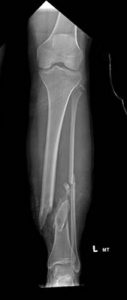

Chapman’s accident resulted in two open fractures in her legs that needed to be stabilized, and she lost a lot of skin that would need coverage, according to her orthopedic surgeon, Dr. Michael Rusnak. He used cement rods as a temporary stabilization that would later be replaced with metal.

“There was tissue damage around the bone, so there was an issue with blood flow,” he said. “I brought in (Dr.) James (McCarthy) to help. This was really a team approach.”

McCarthy covered the exposed rod and bone in Chapman’s right leg with muscle in the area, as he would in most cases. But her body rejected this technique with an infection. McCarthy went back in, transplanting a muscle from Chapman’s back, including its associated vein and artery, and meticulously attached the 2-millimeter blood vessels together — called microsurgery — to return the blood flow to Chapman’s damaged leg. The medical team had to do all of this while also ensuring her legs would have no deformities that could affect her mobility.